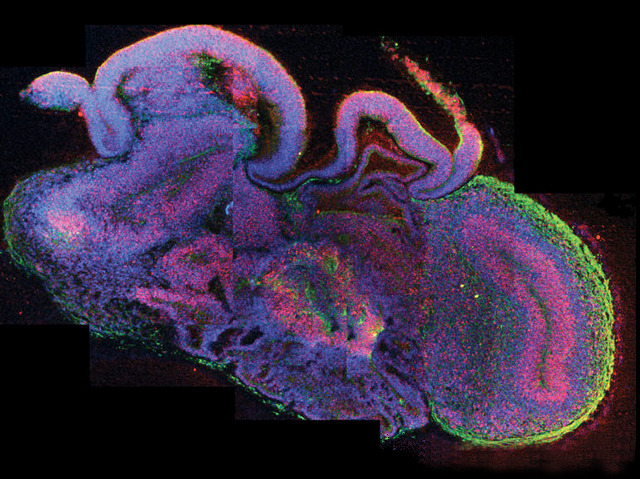

This is a cross-section of a ‘cerebral organoid’ – a lab-grown version of an embryonic human brain. Neural precursors – that become brain cells (neurons) – are highlighted in pink, and neurons in green. Researchers made these tiny brain-like structures by first bathing human induced pluripotent stem cells, which can become any cell in the body, in a cocktail of nutrients that persuade them to become neural precursors. The cells were then embedded in a gel, and later plopped into a special spinning chamber and left to grow. Over 20–30 days, the cells arranged themselves into pea-sized balls of tissue that boast some features of an adult brain. They don’t form neural networks but they do develop distinct regions, including the cerebral cortex, that generate mature neurons in the normal way. Cerebral organoids will be used to study the early development of the human brain and the neurodevelopmental disorders that disrupt it.